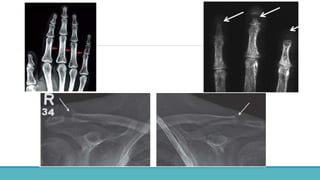

• Cortical bone erosion – Phalanges

•Most sensitive site : Radial aspects of

middle phalanges of index and middle

fingers.

• Tufts of distal phalanges.

•Acrosteolysis – distal phalanges, Outer

clavicle, pubic symphysis, sacroiliac joints,

proximal medial cortex of tibia, proximal

humeral shaft, ribs and femur.

➢Osteoclastic resorption  Cystic lesion in bone.

➢Cavities filled with fibrous tissue and osteoclasts, fibrous

tissue, necrotic and hemorrhagic liquefaction.

➢On x rays : Low density multiloculated cysts

Expansion of bones.

➢ Can be mistaken for neoplastic lesions.

• Cortical boneerosion – Phalanges •Most sensitive site : Radial aspects of middle phalanges of index and middle fingers. • Tufts of distal phalanges. •Acrosteolysis – distal phalanges, Outer clavicle, pubic symphysis, sacroiliac joints, proximal medial cortex of tibia, proximal humeral shaft, ribs and femur.